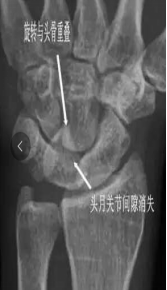

舟月骨缺血性坏死

腕关节发生骨缺血坏死的常见部位为舟骨和月骨

好发于20-30岁手工劳动者,也常见于腕部急性创伤和月骨骨折脱位后

男性多见

X线表现为病变早期骨形态尚可,骨质密度增高,其内可见囊样透亮影,进展期骨质塌陷,周边关节间隙增宽;MR对早期骨缺血坏死较敏感

手足短骨解剖及常见疾病的影像学表现

舟骨缺血性坏死

54Y,M 月骨缺血性坏死

65Y,M,左手疼痛2个月